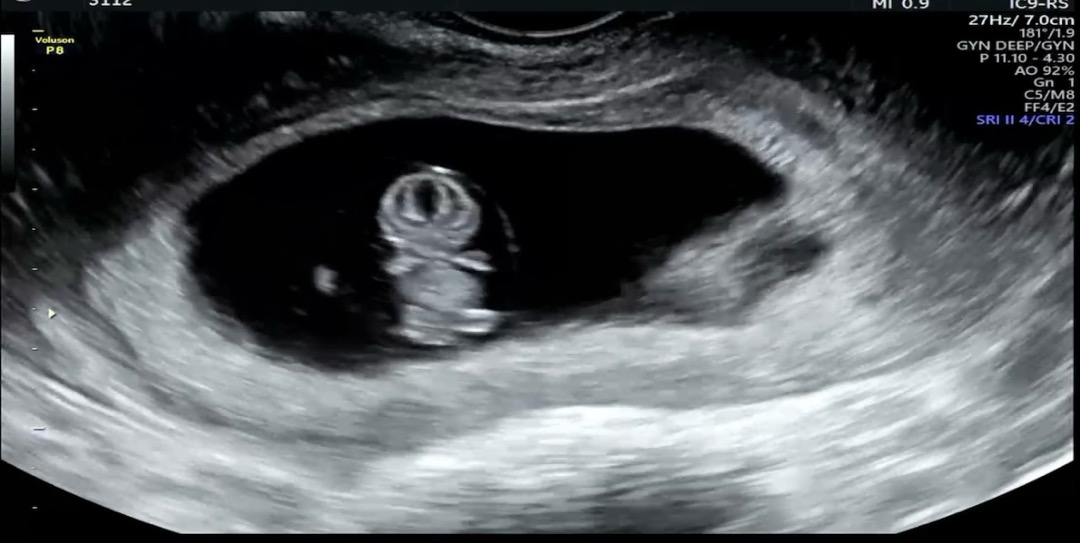

9์ฃผ์์!!!๐ซถ

์๋ฝํ์ธ์~~~~ 9์ฃผ์ฐจ ํ๋ฆฌ๋ณด์ธ์ฌ๋๋ ค์ฉ๐๐ ๋๋์ด ๋ช ์ ์ง๋๊ณ ๋ณ์๊ฐ์ ์ ค๋ฆฌ๊ณฐ๋ณด๊ณ ์์ด์๐ฅน๐ฅน ๊ฐ๊ฒฉ๋๊ฐ๊ฒฉ